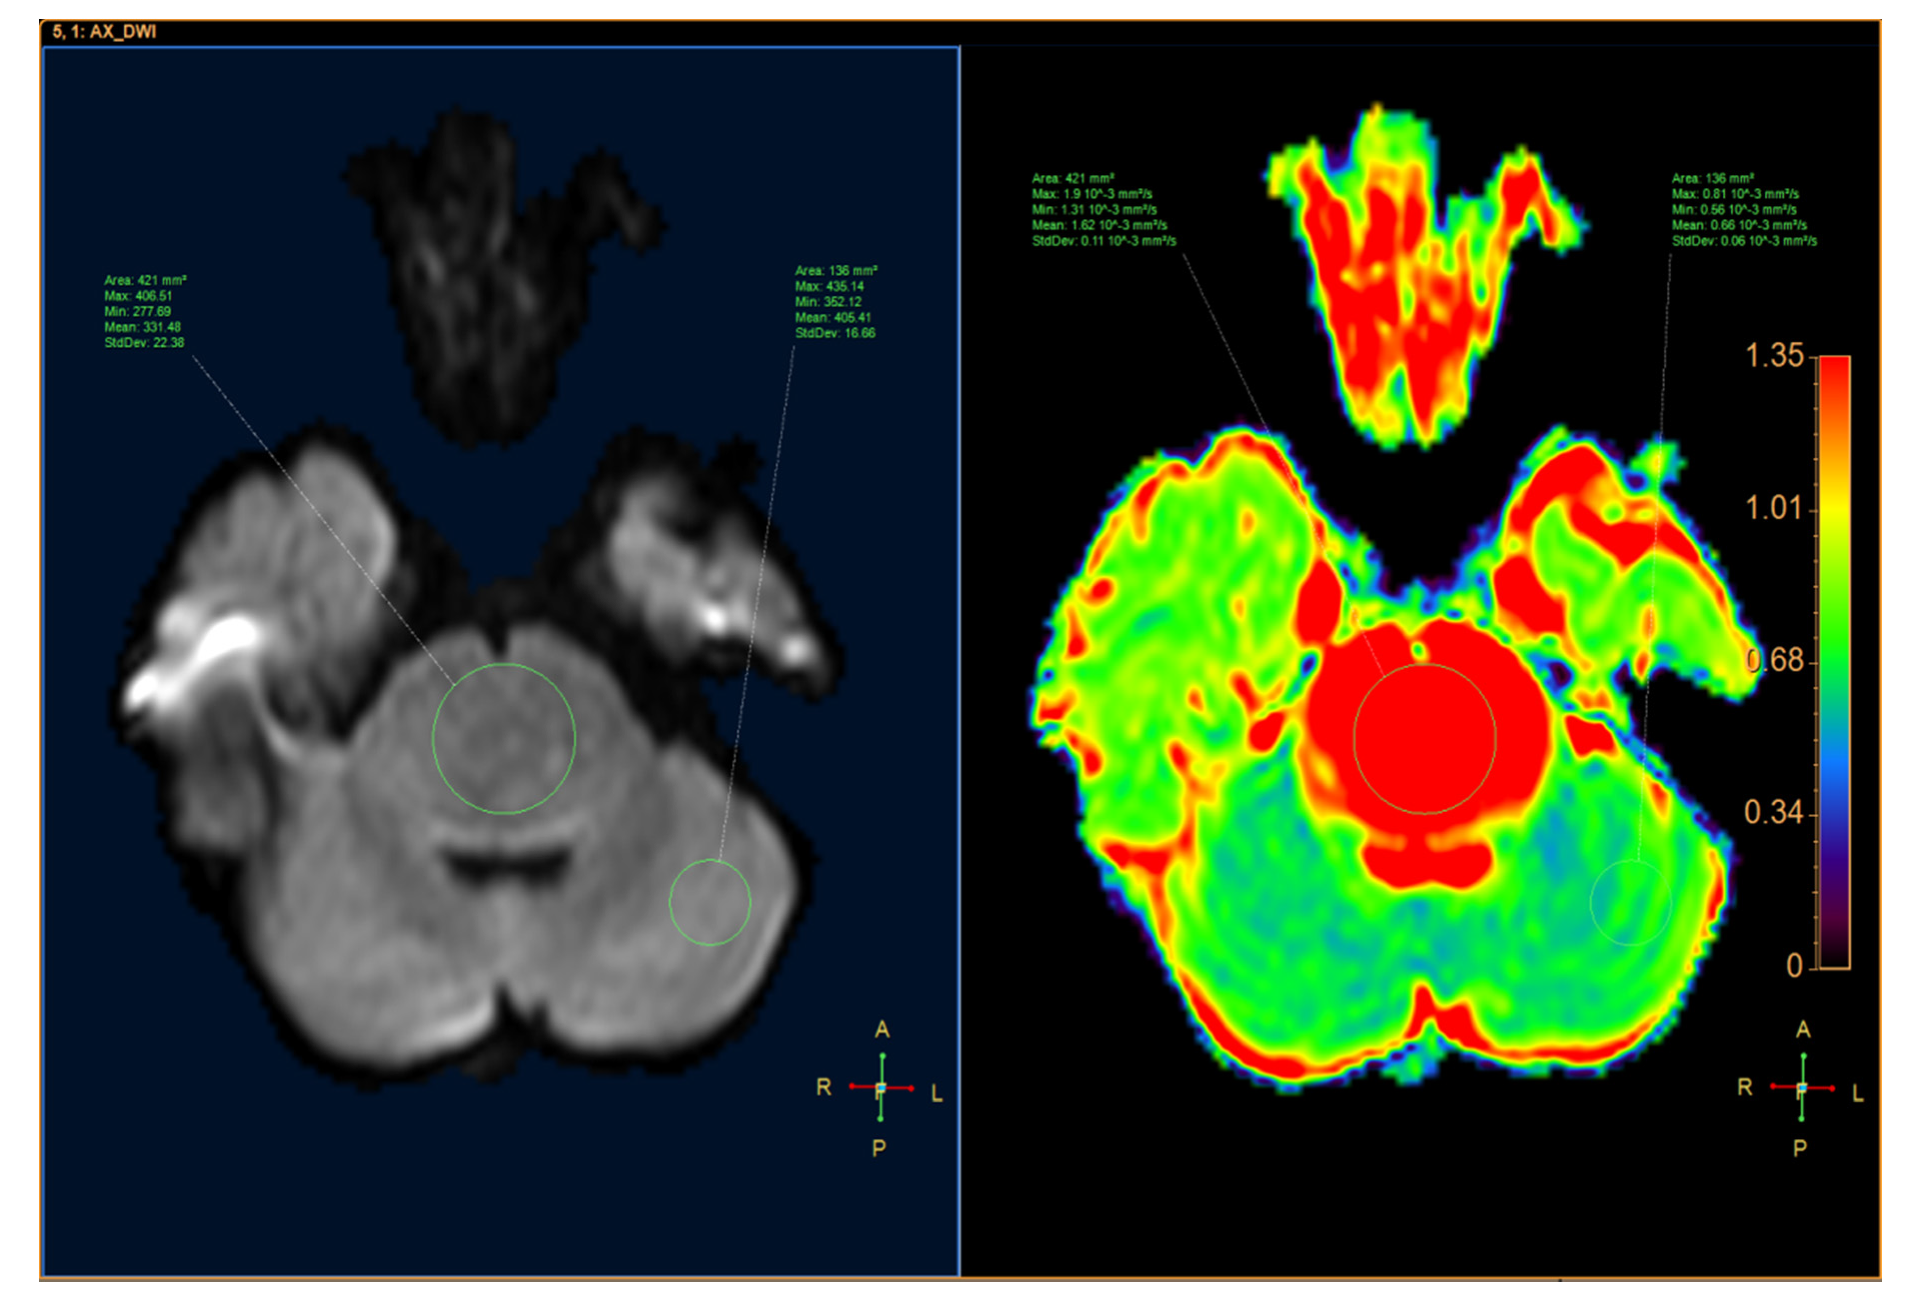

ADC was quantified by defining the region of interest (ROI) for the tumor and the parenchyma on the ADC map with MR Diffusion tool available in Philips Intellispace Portal, version 11 (Philips, Best, The Netherlands). ADC will provide the following parameters: maximum ADC (ADCmax), minimum ADC (ADCmin), mean ADC (ADCmean), and standard deviation ADC (ADCsd). The following additional parameters were also assessed: the ratio of tumor ADCmax to parenchyma ADCmax (rADCmax), the ratio of tumor ADCmin to parenchyma ADCmin (rADCmin), the ratio of tumor ADCmean to parenchyma ADCmean (rADCmean), and the ratio of tumor ADCsd to parenchyma ADCsd (rADCsd) (Figure 1 and Figure 2).

Figure 1.

An 8-year-old male patient had a tumor inside the fourth ventricle, which was confirmed as medulloblastoma after surgery. (Left) Axial diffusion-weighted image (DWI). (Right) apparent diffusion coefficient (ADC) map.